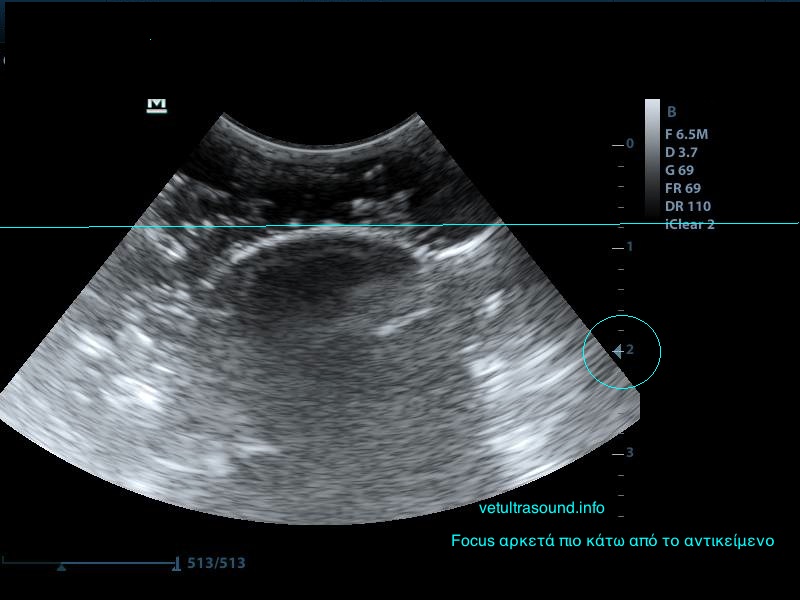

4) Το focus, δηλαδή την εστίαση της δέσμης, όσο πιο κοντά βρίσκεται σε αυτό που θέλουμε να μελετήσουμε τόσο καλύτερη εικόνα έχουμε.